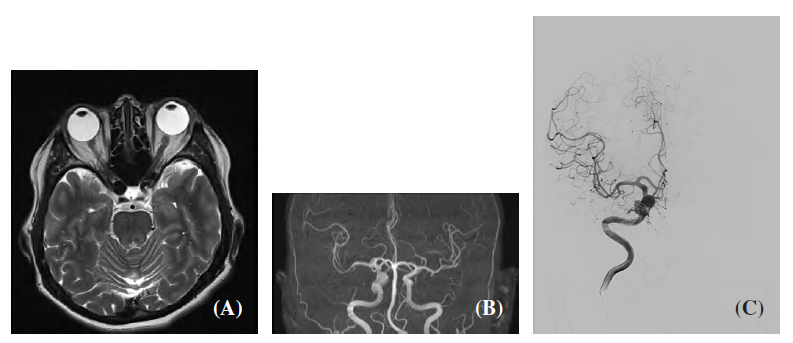

As part of a joint proof-of-concept project, the case of a female patient with an aneurysm in one of the major cerebral arteries was analysed. Computational Fluid Dynamics (CFD) served as a supporting tool in this study, enabling the quantification of parameters such as shear stress, flow oscillations, and blood residence time in a realistic 3D model of the blood vessels created from angiographic data. Based on these calculations, it was possible to compare selected haemodynamic characteristics before and after the procedure.

Visualisation of the patient's blood vessels